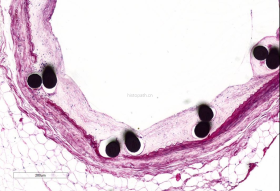

动脉支架

使用德国EXAKT切磨系统进行硬组织切片,特别是对于含有金属这类植入物的组织,是一种精确的组织切片技术。

各类尺寸的含金属植入物骨、牙齿、血管等硬组织样本脱水,7200树脂浸润包埋,后期用标准尺寸(25mm*75mm)的树脂片进行切磨片处理。

将包埋好的硬组织树脂块,用EXAKT 硬组织切片机先切一个200um的厚片,然后再通过EXAKT 硬组织磨片机将其磨到20-30um薄片,样本是已经硬组织包埋好的含金属的动物样本。

针对不同的病理阅片指标需求,行HE染色、Masson染色、亚甲基蓝-酸性品红染色、VG染色、Movat染色等。